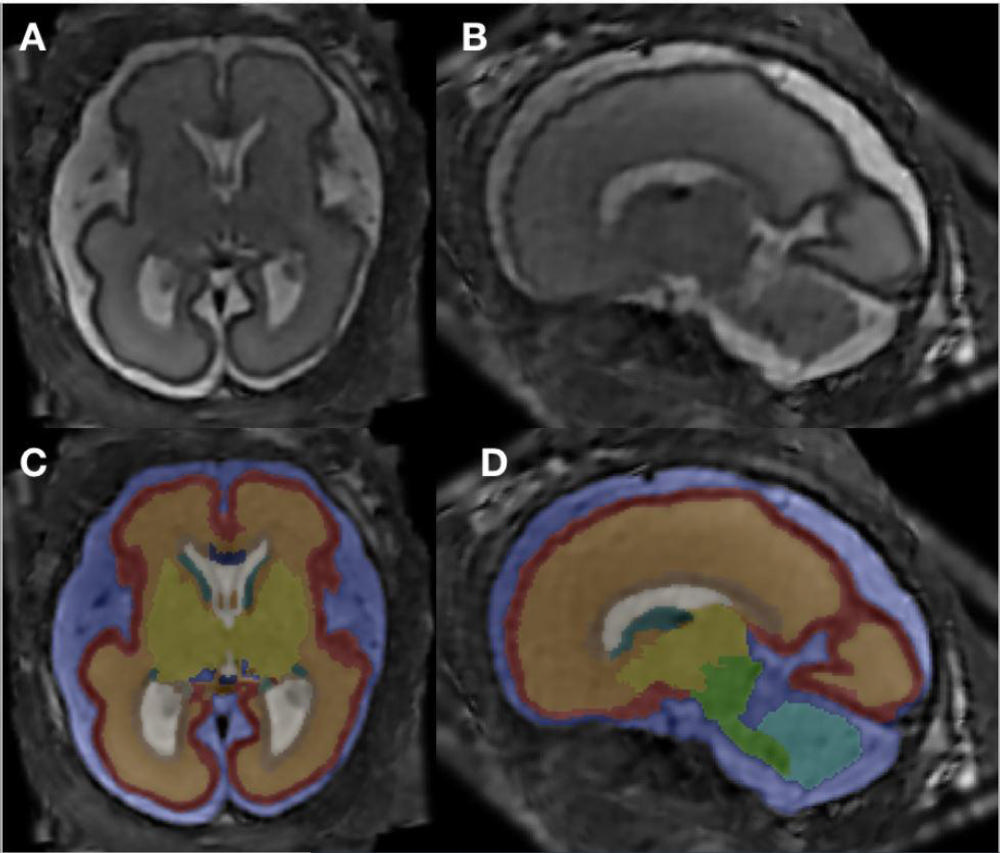

Figure 1. MRI super-resolution reconstruction and atlas-based tissue segmentation. (A, B) Postprocessed MRI super-resolution reconstructions in axial and sagittal planes of a fetus at 26+6 GW. (C, D) Respective manually corrected atlas-based tissue segmentation.

Color coding: blue - external CSF-spaces, red - cortex, orange - subcortical parenchyma, brown - periventricular zone, dark green - ganglionic eminence, white - ventricular system, dark blue - corpus callosum, yellow – deep gray nuclei (basal ganglia and thalamus), light green - brainstem, light blue - cerebellum, turquoise - left hippocampus, gray - right hippocampus.